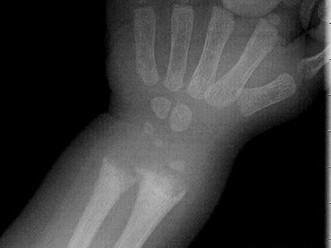

男,2岁,关节浮肿,请结合图像,选出最可能的诊断 ( )A、维生素C缺乏症B、维生素D过多症C、MPSD、维生素D缺乏症E、肾性骨病

问题 男,2岁,关节浮肿,请结合图像,选出最可能的诊断 ( )

选项 A、维生素C缺乏症 B、维生素D过多症 C、MPS D、维生素D缺乏症 E、肾性骨病

答案 E